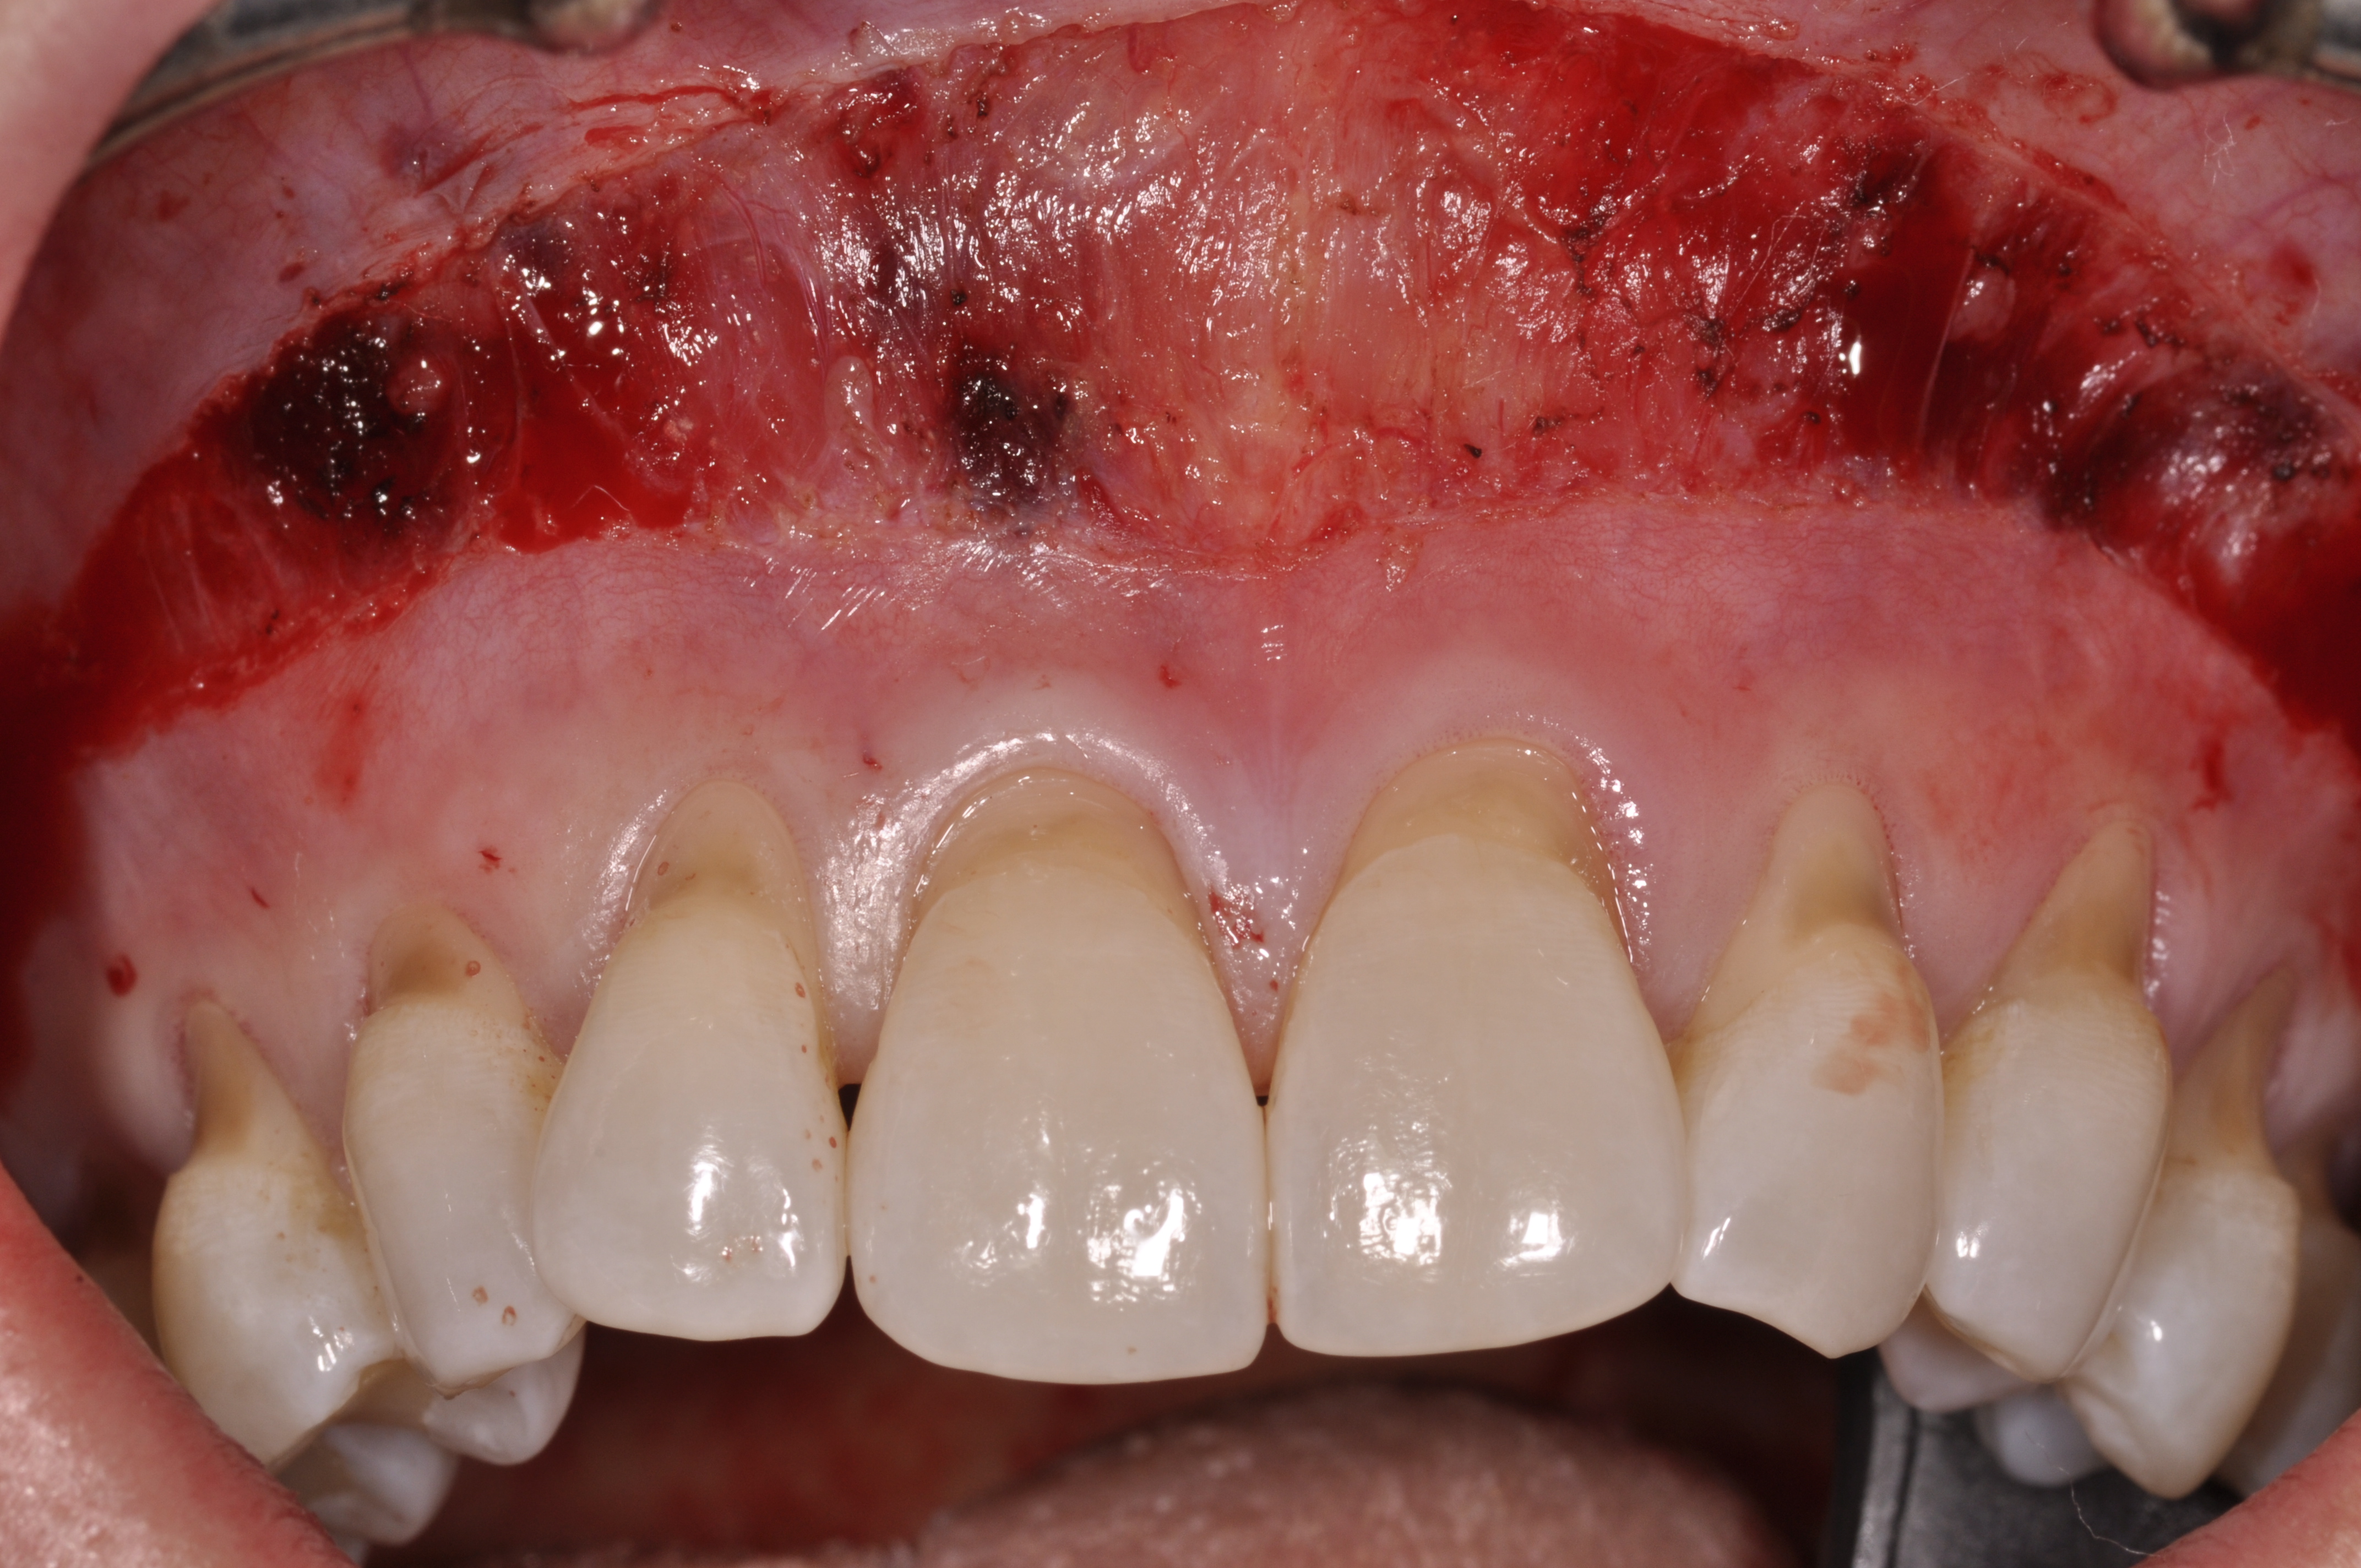

Closure was then accomplished by coronally repositioning the buccal flap and securing the flap using an interrupted sling suturing technique with 5.0 Monocryl™ (Ethicon, www.ethicon.com). The interrupted sling suture technique was started at the mesial aspect of each tooth in the area of the mucogingival junction, and passed interproximally to the distal aspect of the same tooth; the flap was then engaged in the mucogingival junction area, and the suture was passed back interproximally at the distal aspect palatally, then to the buccal from the mesial aspect of the tooth. The suture was then tied off at the mesial aspect. This closure technique was performed for each of the affected tooth sites (Figure 12 and Figure 13).

Once the flap was coronally repositioned and secured, a securing periosteal tac procedure was performed to prevent any micro movement superior to the mucogingival junction in the initial healing phase. A 4.0 chromic gut suture (Surgical Specialties Corp.) was used to engage the periosteum superior to the mucogingival junction and stabilize the tissues superior to the securing suture (Figure 12 and Figure 13). Multiple periosteal tac sutures may be necessary, depending on the size of the surgical field. Postoperatively, the periosteal tac sutures are routinely removed if not totally absorbed at 7 days; the flap sutures are removed at 2 to 3 weeks, and dermal-securing sutures are removed 1 month after surgery. The 1-year post-treatment clinical view shown in Figure 14 depicts the excellent soft-tissue result, band of attached keratinized tissue present, and excellent color match to the host gingival tissues.

Fig 12. Closure, lateral view, of case presented.

Figure 12

Fig 13. Closure, frontal view, of case presented.

Figure 13